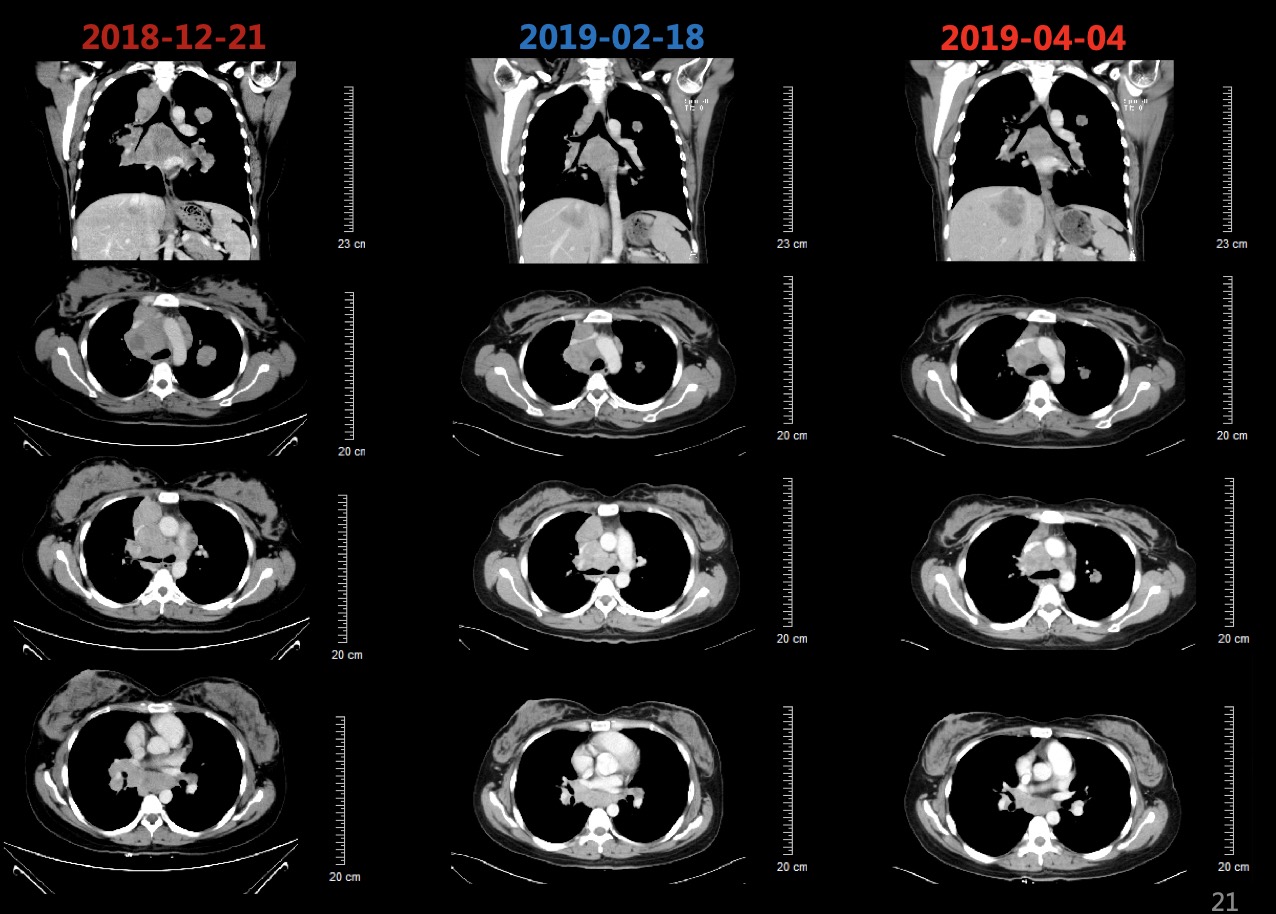

图1 患者基线肺部CT影像,右肺上叶近肺门处团块状软组织密度影,考虑中央型肺癌可能,伴阻塞性肺炎,并纵隔内、双侧肺门多发淋巴结转移,双肺、肝脏多发转移瘤;L1椎体及左侧附件密度增高,考虑为转移瘤;脾大

患者于2018-12-26、2019-01-19分别行第1-2周期TC方案(紫杉醇脂质体+卡铂,每3周1次),患者基线和化疗后肿瘤标志物变化如图3所示,肺和肝脏病灶变化影像如图4所示,2019-02-18复查CT提示肺部病灶稳定(缩小),肝脏病灶增多增大,总体疗效评价疾病进展(PD)。

2019-02-19、2019-03-14行二线贝伐珠单抗+多西他赛化疗(贝伐珠单抗+多西他赛,每3周1次)。2019-03患者开始出现腰部疼痛,考虑为L1椎体骨转移导致,2019-03-19开始行腰骶部局部放疗,2019-04-04复查CT结果如图5所示,肺部病灶稳定(部分缩小),肝脏病灶增多增大、T9-T12椎体新发转移瘤,总体疗效评价(PD)。

患者初治时行PD-L1(22C3)检测提示PD-L1高表达为95%,故建议患者行三线免疫治疗。由于药物可及性,患者综合考虑后,选择信迪利单抗。患者于2019-04-04、2019-04-26、2019-05-18分别行第1~3周期免疫联合化疗三线方案(信迪利单抗+白蛋白紫杉醇 ,每3周1次)。2019-05-18复查肺部CT如图6所示,2019-05-18复查CT:肺部病灶较前明显缩小,阻塞性肺炎较前好转、肝脏病灶较前明显缩小。T2、T9-L2椎体及L2左侧附件多发骨转移同前。

图6 2019-05-18复查胸腹部CT提示肺部病灶较前明显缩小,阻塞性肺炎较前好转、肝脏病灶较前明显缩小。T2、T9-L2椎体及L2左侧附件多发骨转移基本同前